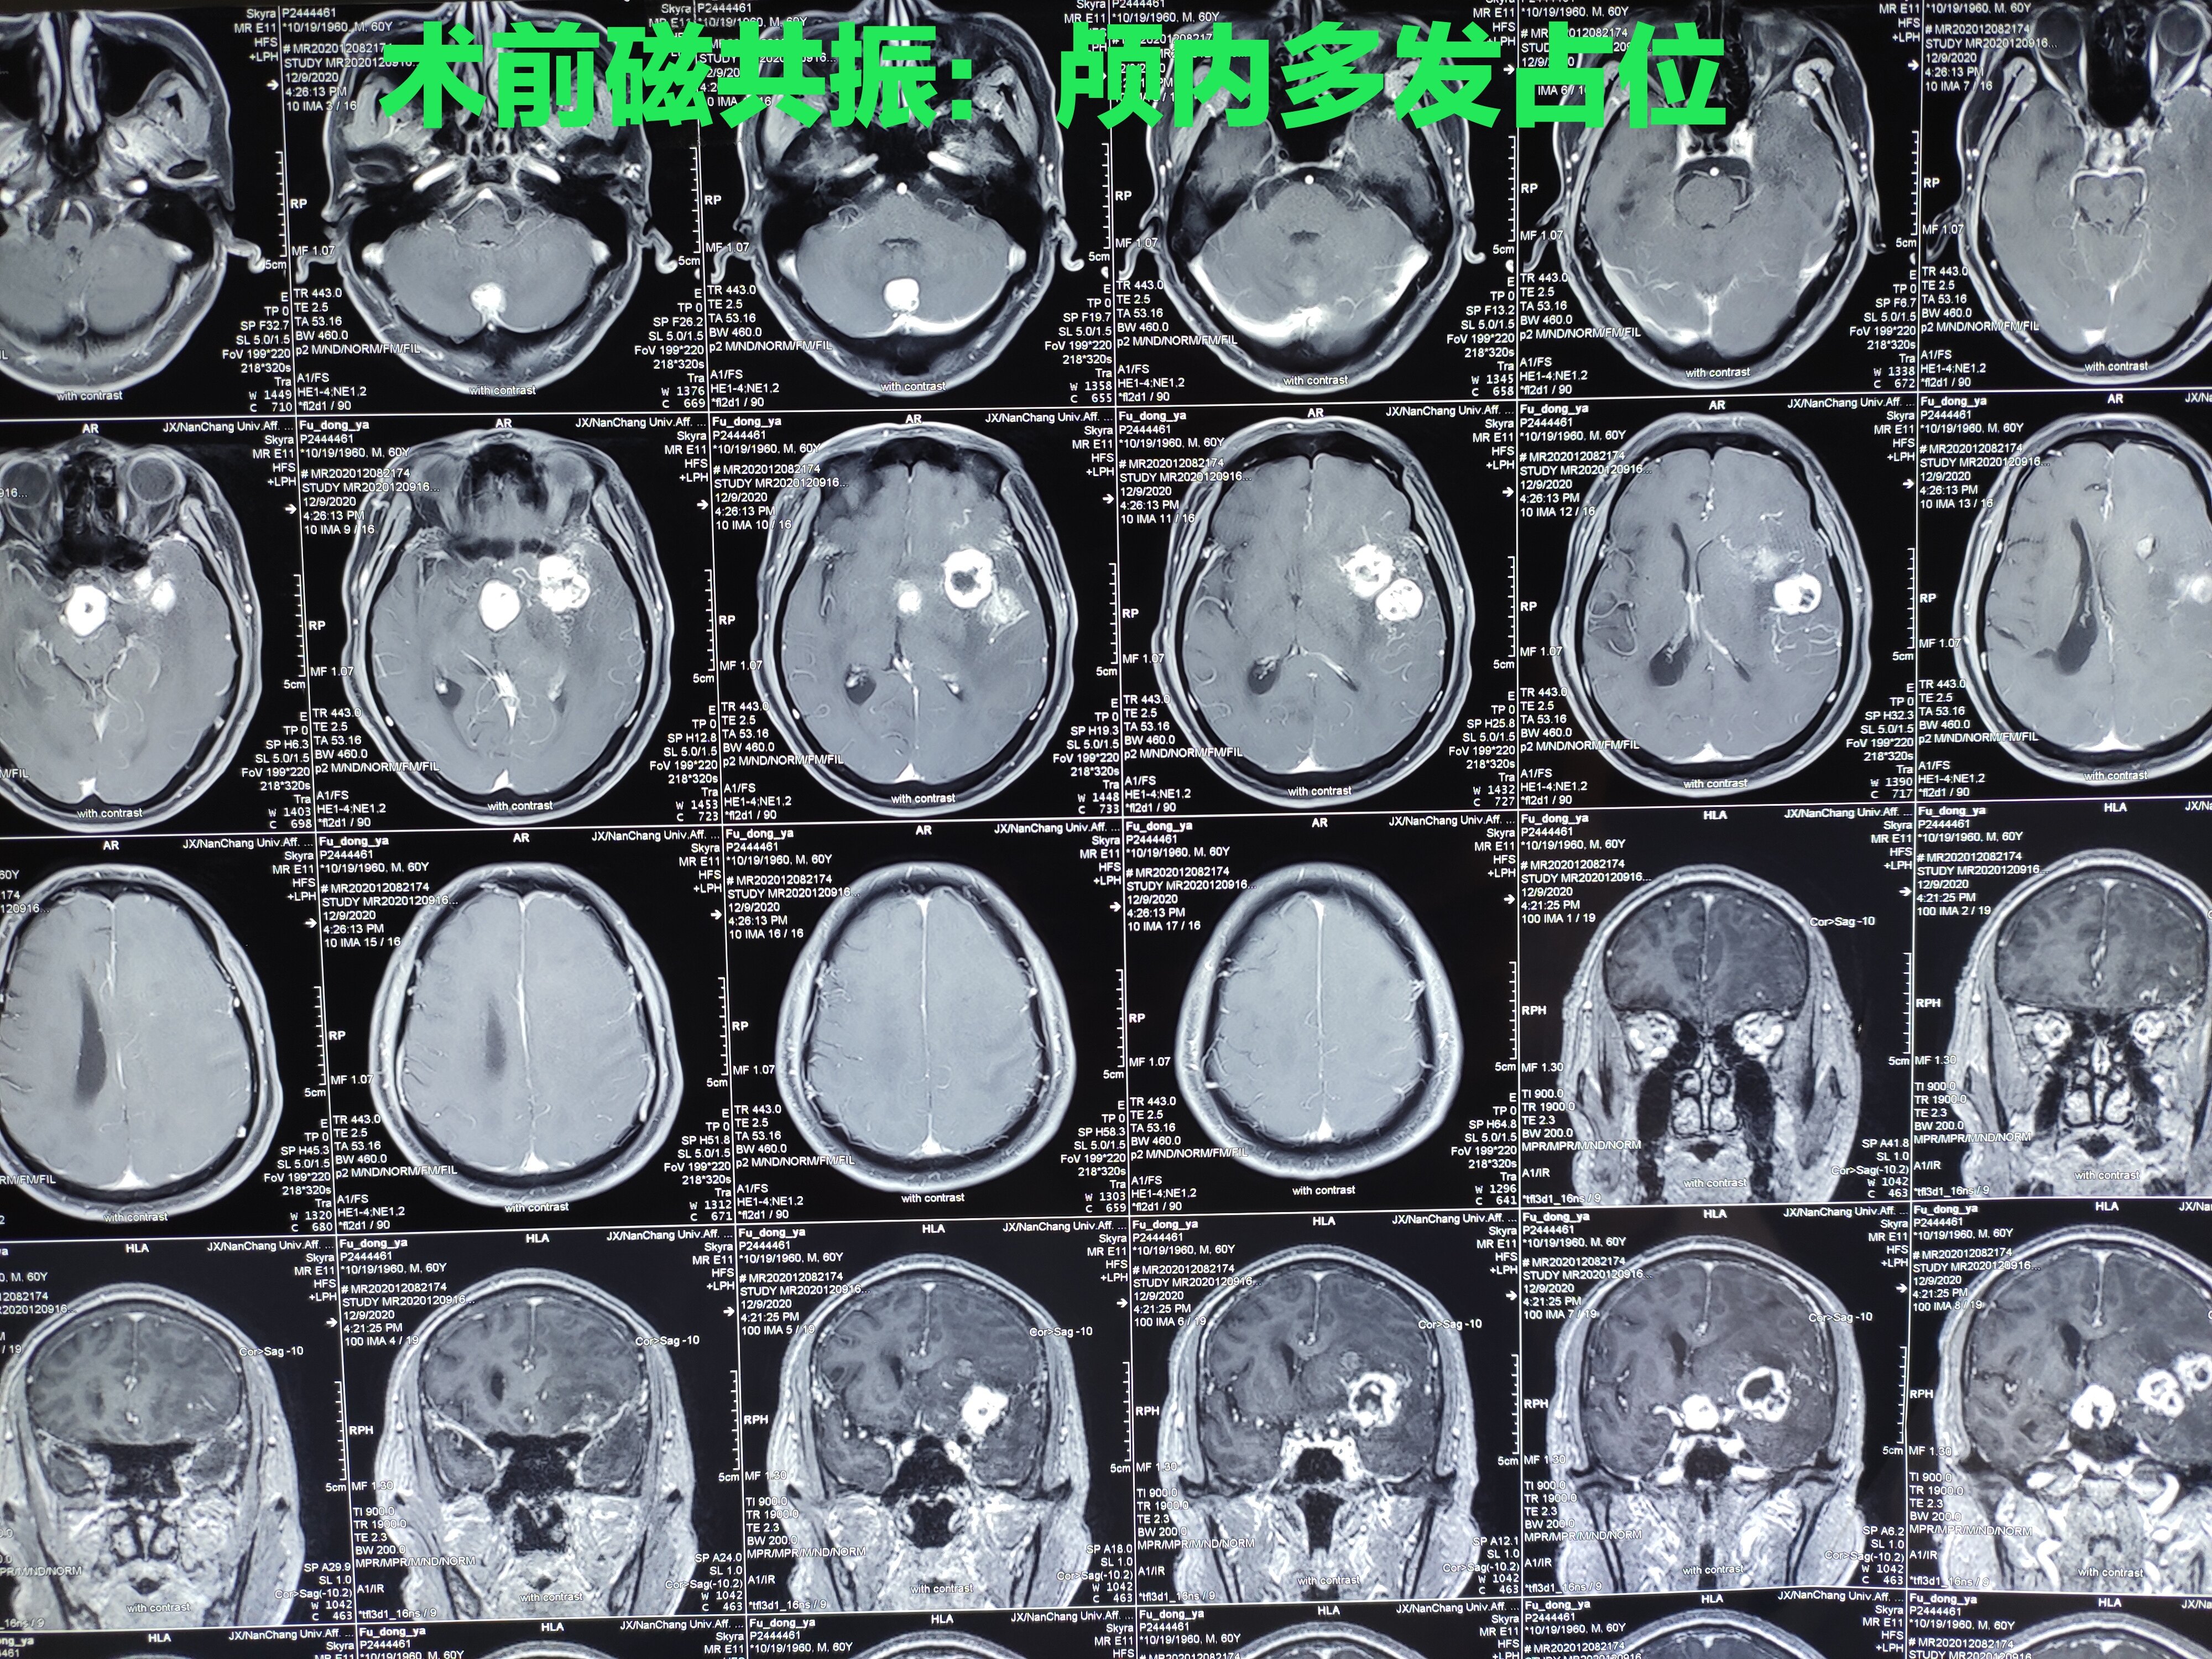

术前脑恶性肿瘤术后病理良性肿瘤 - 好大夫在线

图片尺寸4000x3000

这也是我们临床上经常遇到的一类患者:早期发现良性肿瘤,但没有症状